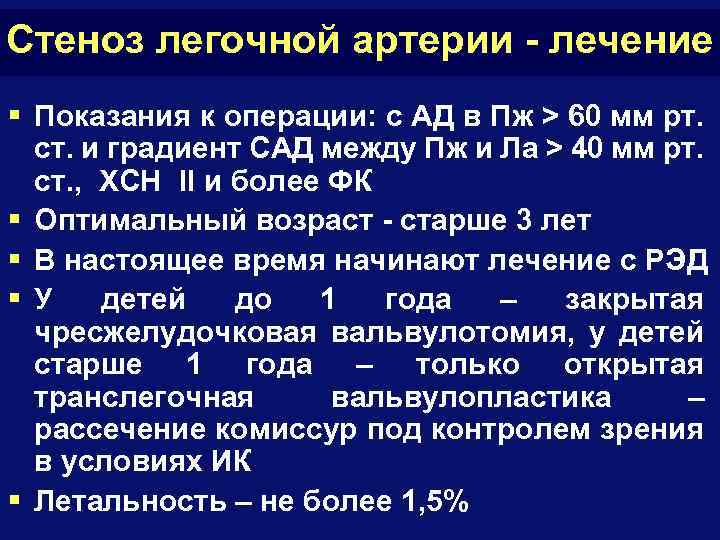

Стеноз легочной артерии - лечение § Показания к операции: с АД в Пж > 60 мм рт. § § ст. и градиент САД между Пж и Ла > 40 мм рт. ст. , ХСН II и более ФК Оптимальный возраст - старше 3 лет В настоящее время начинают лечение с РЭД У детей до 1 года – закрытая чресжелудочковая вальвулотомия, у детей старше 1 года – только открытая транслегочная вальвулопластика – рассечение комиссур под контролем зрения в условиях ИК Летальность – не более 1, 5%